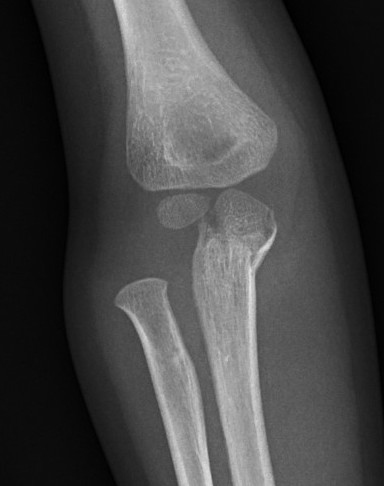

Case 2. Chronic Monteggia with deformed radial head